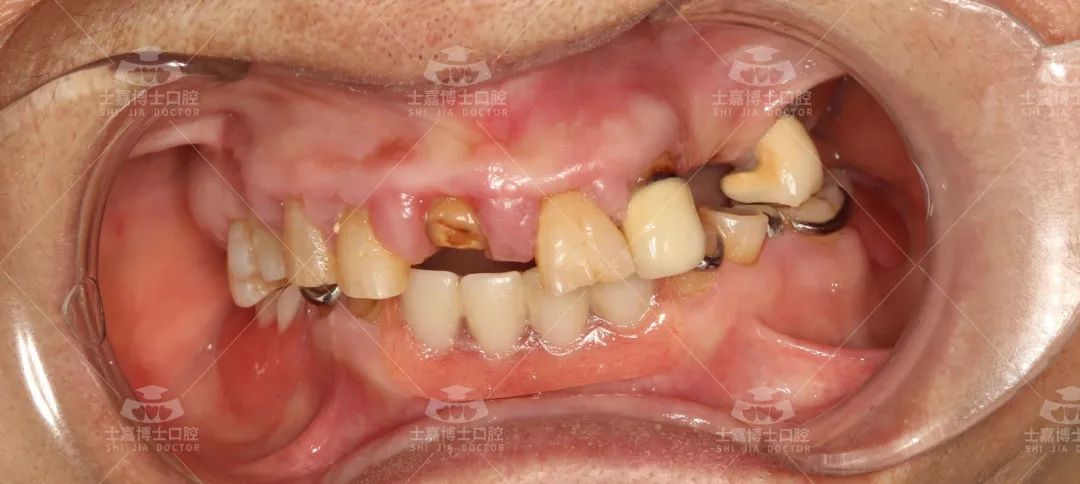

老掉牙并不是正常现象 2022.08.19 有的人到了老年,牙周组织萎缩、牙根暴露以致牙齿松动、脱落,出现“老掉牙”的现象。那么人老了,就一定要掉牙吗? 其实并非如此。恰恰相反,许多人到八九十岁,牙齿照样很好;而有些人四五十岁,还不到“老”就掉牙了,原因何在?医学研究表明,牙齿不是“老”掉的,而是牙周病所致。 舒适化种植前 何阿姨还没到花甲之年,能正常使用的牙齿剩下的就不多了了。最近,又有一颗牙齿的牙龈发炎,让她吃不好也睡不着。何阿姨去医院拔牙,医生建议她吃点药缓解一下病情,先不要把牙齿拔掉,但何阿姨却坚持拔掉。她认为,人老了,牙齿总会掉的,与其让牙齿自行脱落折磨自己,不如主动拔掉。 “老掉牙”是老年人口腔保健的一种错误观念,掉牙与年龄并不成正比,80岁拥有20颗牙齿不是梦。不少老年人牙齿的脱落或被拔除,是由于对牙病不重视所造成的。如果早期积极防治牙病,老年人也会有一口健康的牙齿。 牙齿掉了要及时种 2022.08.19 第二次全国口腔健康流行病学调查结果显示,在65~74岁的老年人中,65%的老年人有龋齿;超过99%的老年人的牙周组织不健康;老年人口腔中现有的牙齿数平均为18颗,而口腔中至少要有20颗功能牙才能保证咀嚼功能。 舒适化种植后 牙周病是牙齿功能丧失的主要原因。如果老年人不注意清洁口腔的话,食物的残渣留在牙齿上,引起牙龈发炎,不及时处理,会一直延伸下去,造成牙龈沟发炎、加深,引起牙槽和牙骨质间隙,形成牙周带,继续下去,牙槽骨被吸收,高度变低,牙齿就越来越松动,时间长了就会脱落。预防牙周病是防止牙齿脱落的关键因素。缺牙不及时去镶,是老人中较常见的通病。 舒适化种植理念 如果老年人的牙齿脱落不及时镶牙,会引起两边的牙齿外倒,牙间隙增大,引起牙周炎,其他牙齿也会松动。 但是由于老人多数年龄较大,对于牙齿种植手术都存在着担忧心理。士嘉博士口腔医院作为第一家舒适化理念治疗的医院,倡导舒适化睡眠牙齿种植治疗,对于患有心脑血管病、高血压及牙科恐惧症患者而言是非常好的就诊选择,就像无痛胃镜一样,让您在无痛舒适化睡眠中完成所有口腔治疗。 士嘉博士口腔医院引进了德国卡瓦牙科综合治疗椅、德国卡瓦3D数字化影像设备、德国3D瓷睿刻数字化牙椅旁修复系统、德国3D打印数字化种植导板系统、瑞士美国德国韩国等世界品牌种植系统等 能够提供当天就诊、当天戴牙,大大缩短了患者的等待时间。个性化服务更好,义齿生产质量更精密,还能快速解决临床戴牙所遇到的问题,效率高、客户满意度大大提高 保持口腔洁净 有利牙齿健康 2022.08.19 老年人应加强口腔保健,做到饭后、睡前刷牙,及时清除牙面、牙缝中的菌斑和食物残渣;要用保健牙刷正确刷牙,即采用上牙向下剔刷、下牙向上剔刷的竖刷法。 定期洗牙对老人来说也很重要。日本的一位口腔专家提出,老年人最好半年定期洗一次牙。因为,随着老年人全身组织器官的衰老,唾液分泌量减少,对口腔的自洁作用就减弱了。洗牙能够清洁刷牙时刷不到的部位,彻底清除牙菌斑、牙结石等。 此外,老年人定期进行口腔检查很有必要。老年人至少应该每年做一次口腔检查。龋齿和牙周病在早期没有明显的自觉症状,只有定期进行口腔检查才能做到早发现、早治疗 昨天8.19日,是专属医务人员的节日 中国医师节是经国务院同意设立的卫生与健康工作者的节日,体现了党和国家对1100多万卫生与健康工作者的关怀和肯定。 在这边再次祝所有医护人员节日快乐~